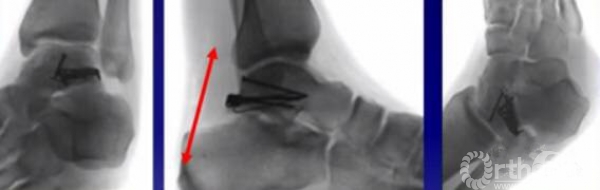

损伤主要位于以下几个主要部分:体、颈、后突、外突

当发生骨折脱位时,由于位移巨大,导致相应位移的血管损伤、最终导致距骨坏死,所以距骨骨折的分型常用Hawkins分型,距骨坏死率随分型严重程度逐渐增加。

移位的体部骨折和II-IV型(2mm以上)的颈部骨折移位

如果一侧钢板的位置不佳,则容易造成另外一侧的骨折裂开。所以最好的固定是一侧用钢板固定,另外一侧可采用螺钉进行加压,对于颈部的骨折,避免另外一侧开口。